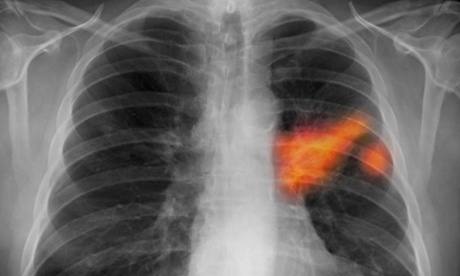

A chest x-ray showing cancer in the left lung. Photograph: Kallista Images